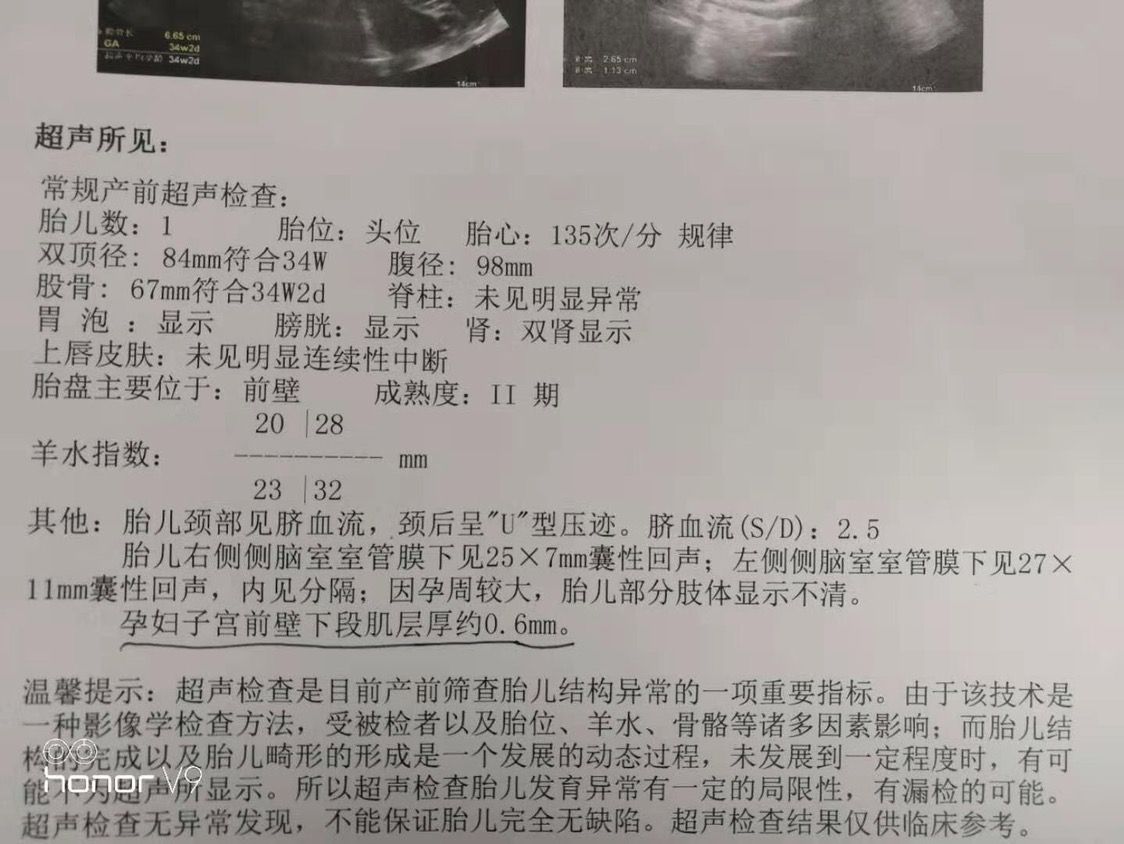

孕期胎儿B超提示脑室增宽及囊肿